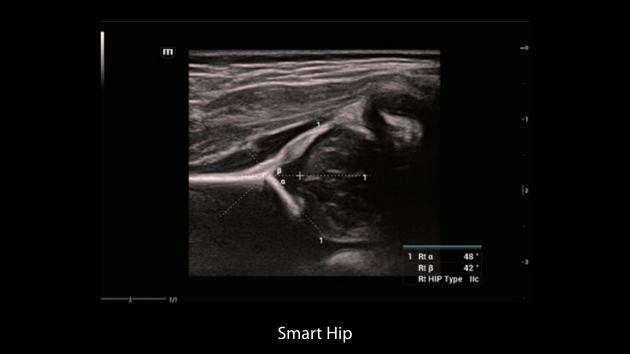

Nuewa I9? ??? ???? ?? ??? ?? ??? ???? ?? ??? ???? ???? ??? ?????. ??? ??? ??? ?? ????? ?? ???? ???? ???? ???? ??? ???? ??? ??? ???? ??? ???? ??? ?? ?????.

ZST+ ???? ???? ??? ???? ??? ?????. ??? ????? ??? ? ???? ?? ??? ?? ????? ?????. ?? ???, ?? ???, ?? ??? ?? ?? ?? ??? ??? ???? ???? ??? ?? ??? ?? ???? ?? ??? ?? ??? ?????.